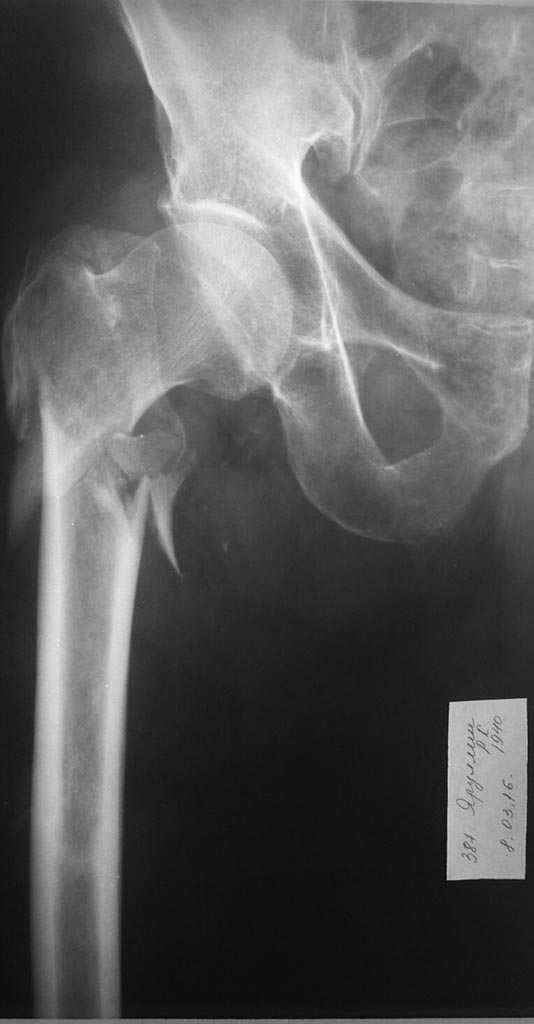

Имя     : IMG-20160308-WA0004.jpg